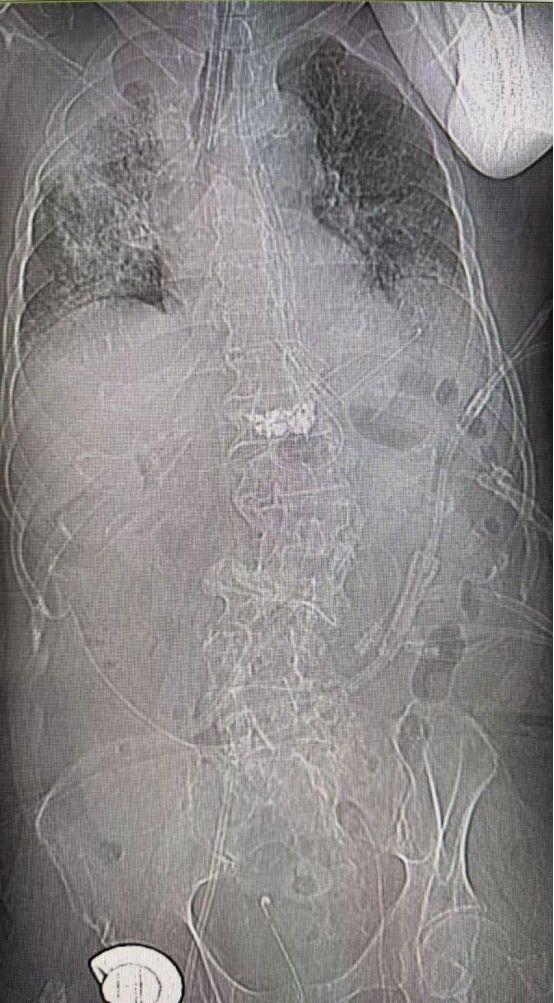

8月26日复查CT平片。腹部及肺部已经有明显改善。(及时复查床旁X片)。经过全面系统的治疗,于8月29日成功脱离呼吸机、拔除气管插管,改为高流量吸氧,随后逐步给予调整氧浓度。9月1日改为鼻导管吸氧,重症肺炎和脓毒症得到了有效控制,于9月2日转回普通外科继续治疗。从马先生住进重症医学科(ICU)那一刻起,全科的医护人员就投入到紧张的工作中。医生们仔细地询问完善老人的病史,进行全面的检查,不放过任何一个细节。多次组织会诊,分析讨论为其提供最适合患者的治疗方案。全科护士们24小时床旁坚守,密切观察老人的病情变化,及时为老人翻身,拍背,压疮护理,实时监护。同时,家属们与医务人员始终保持了良好密切的沟通,及时对老人的病情进展提供必要支持,医生和家属之间共同为老人的治疗、康复努力着。在这个普通平凡的ICU病房里,因为这位98岁的老人,全科的医护人员和家属的心紧紧地贴在了一起。最后小编想说,每一位患者的成功救治都离不开医护人员的努力,更离不开家属的支持和理解。